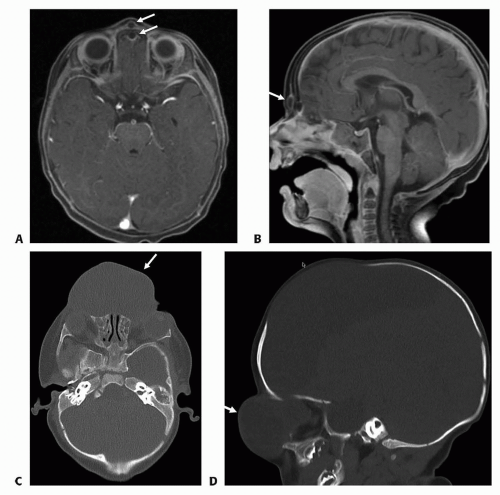

Typical imaging findings (FIG 3):

Interorbital distance—widened

Frontonasal cranial defect

Nasal bone—displaced and angulated

Bifid crista galli